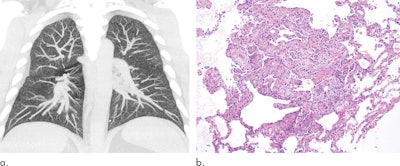

Nonetheless, the medical community and governmental bodies have been able to produce preliminary guidelines to facilitate the early detection of EVALI, especially through pulmonary imaging. The general consensus among lung imaging experts is to use x-ray followed by CT or CT pulmonary angiography, where necessary, to identify key imaging patterns indicative of EVALI.

The researchers found that the most common radiologic findings associated with EVALI thus far have been organizing pneumonia and diffuse alveolar damage, followed by diffuse alveolar hemorrhage and acute eosinophilic pneumonia, all of which they previously explored in depth during a special interest session at RSNA 2019. Other imaging patterns mentioned in reports include hypersensitivity pneumonitis, exogenous lipoid pneumonia, and giant cell interstitial pneumonia, though the group recommended that these less-common patterns not be qualified as signs of EVALI just yet.